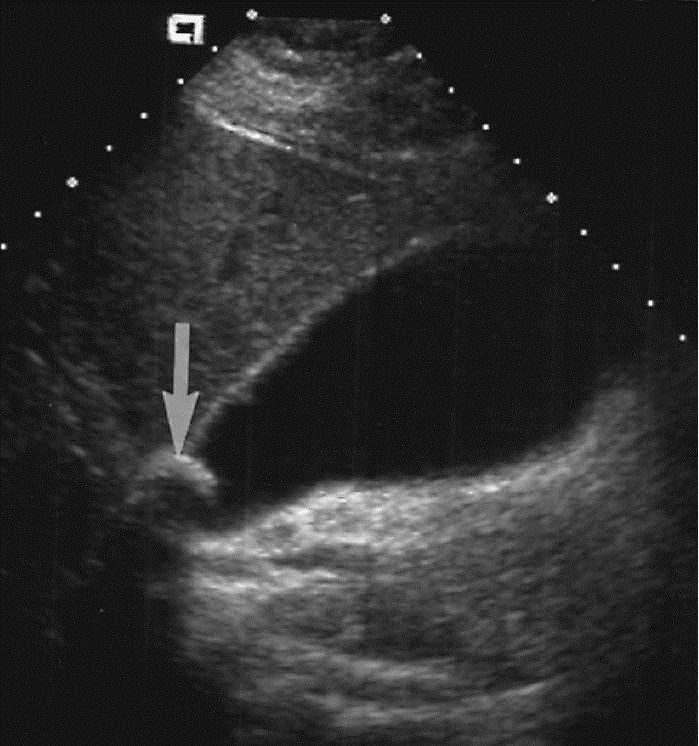

УЗИ желчного пузыря. Стрелкой показан камень желчного пузяря.

Диагноз ЖКБ ставится на основе УЗИ и (или) рентгенологического исследования желчного пузыря – холецистографии.

В настоящее время УЗИ желчного пузыря при диагностике ЖКБ стал методом выбора. Преимуществом УЗИ является неинвазивный характер метода, отсутствие лучевой нагрузки, мобильность и не требует специальной подготовки больному. Достаточно пациенту воздержаться от питания 12 часов. Чувствительность и специфичность метода при диагностике ЖКБ равна примерно 95%. Современными аппаратами УЗИ можно выявить камни до 2 мм.